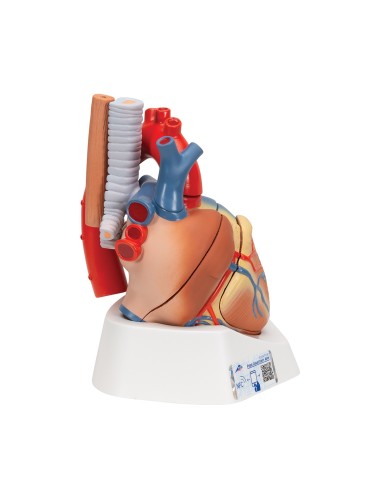

Su Base, staccabile

Con scheda descrittiva dettagliata

Su base removibile

Realizzato in stampa 3D ad elevatissima risoluzione a colori.

Realizzato in stampa 3D ad elevatissima risoluzione a colori.

Realizzato in stampa 3D ad elevatissima risoluzione a colori.